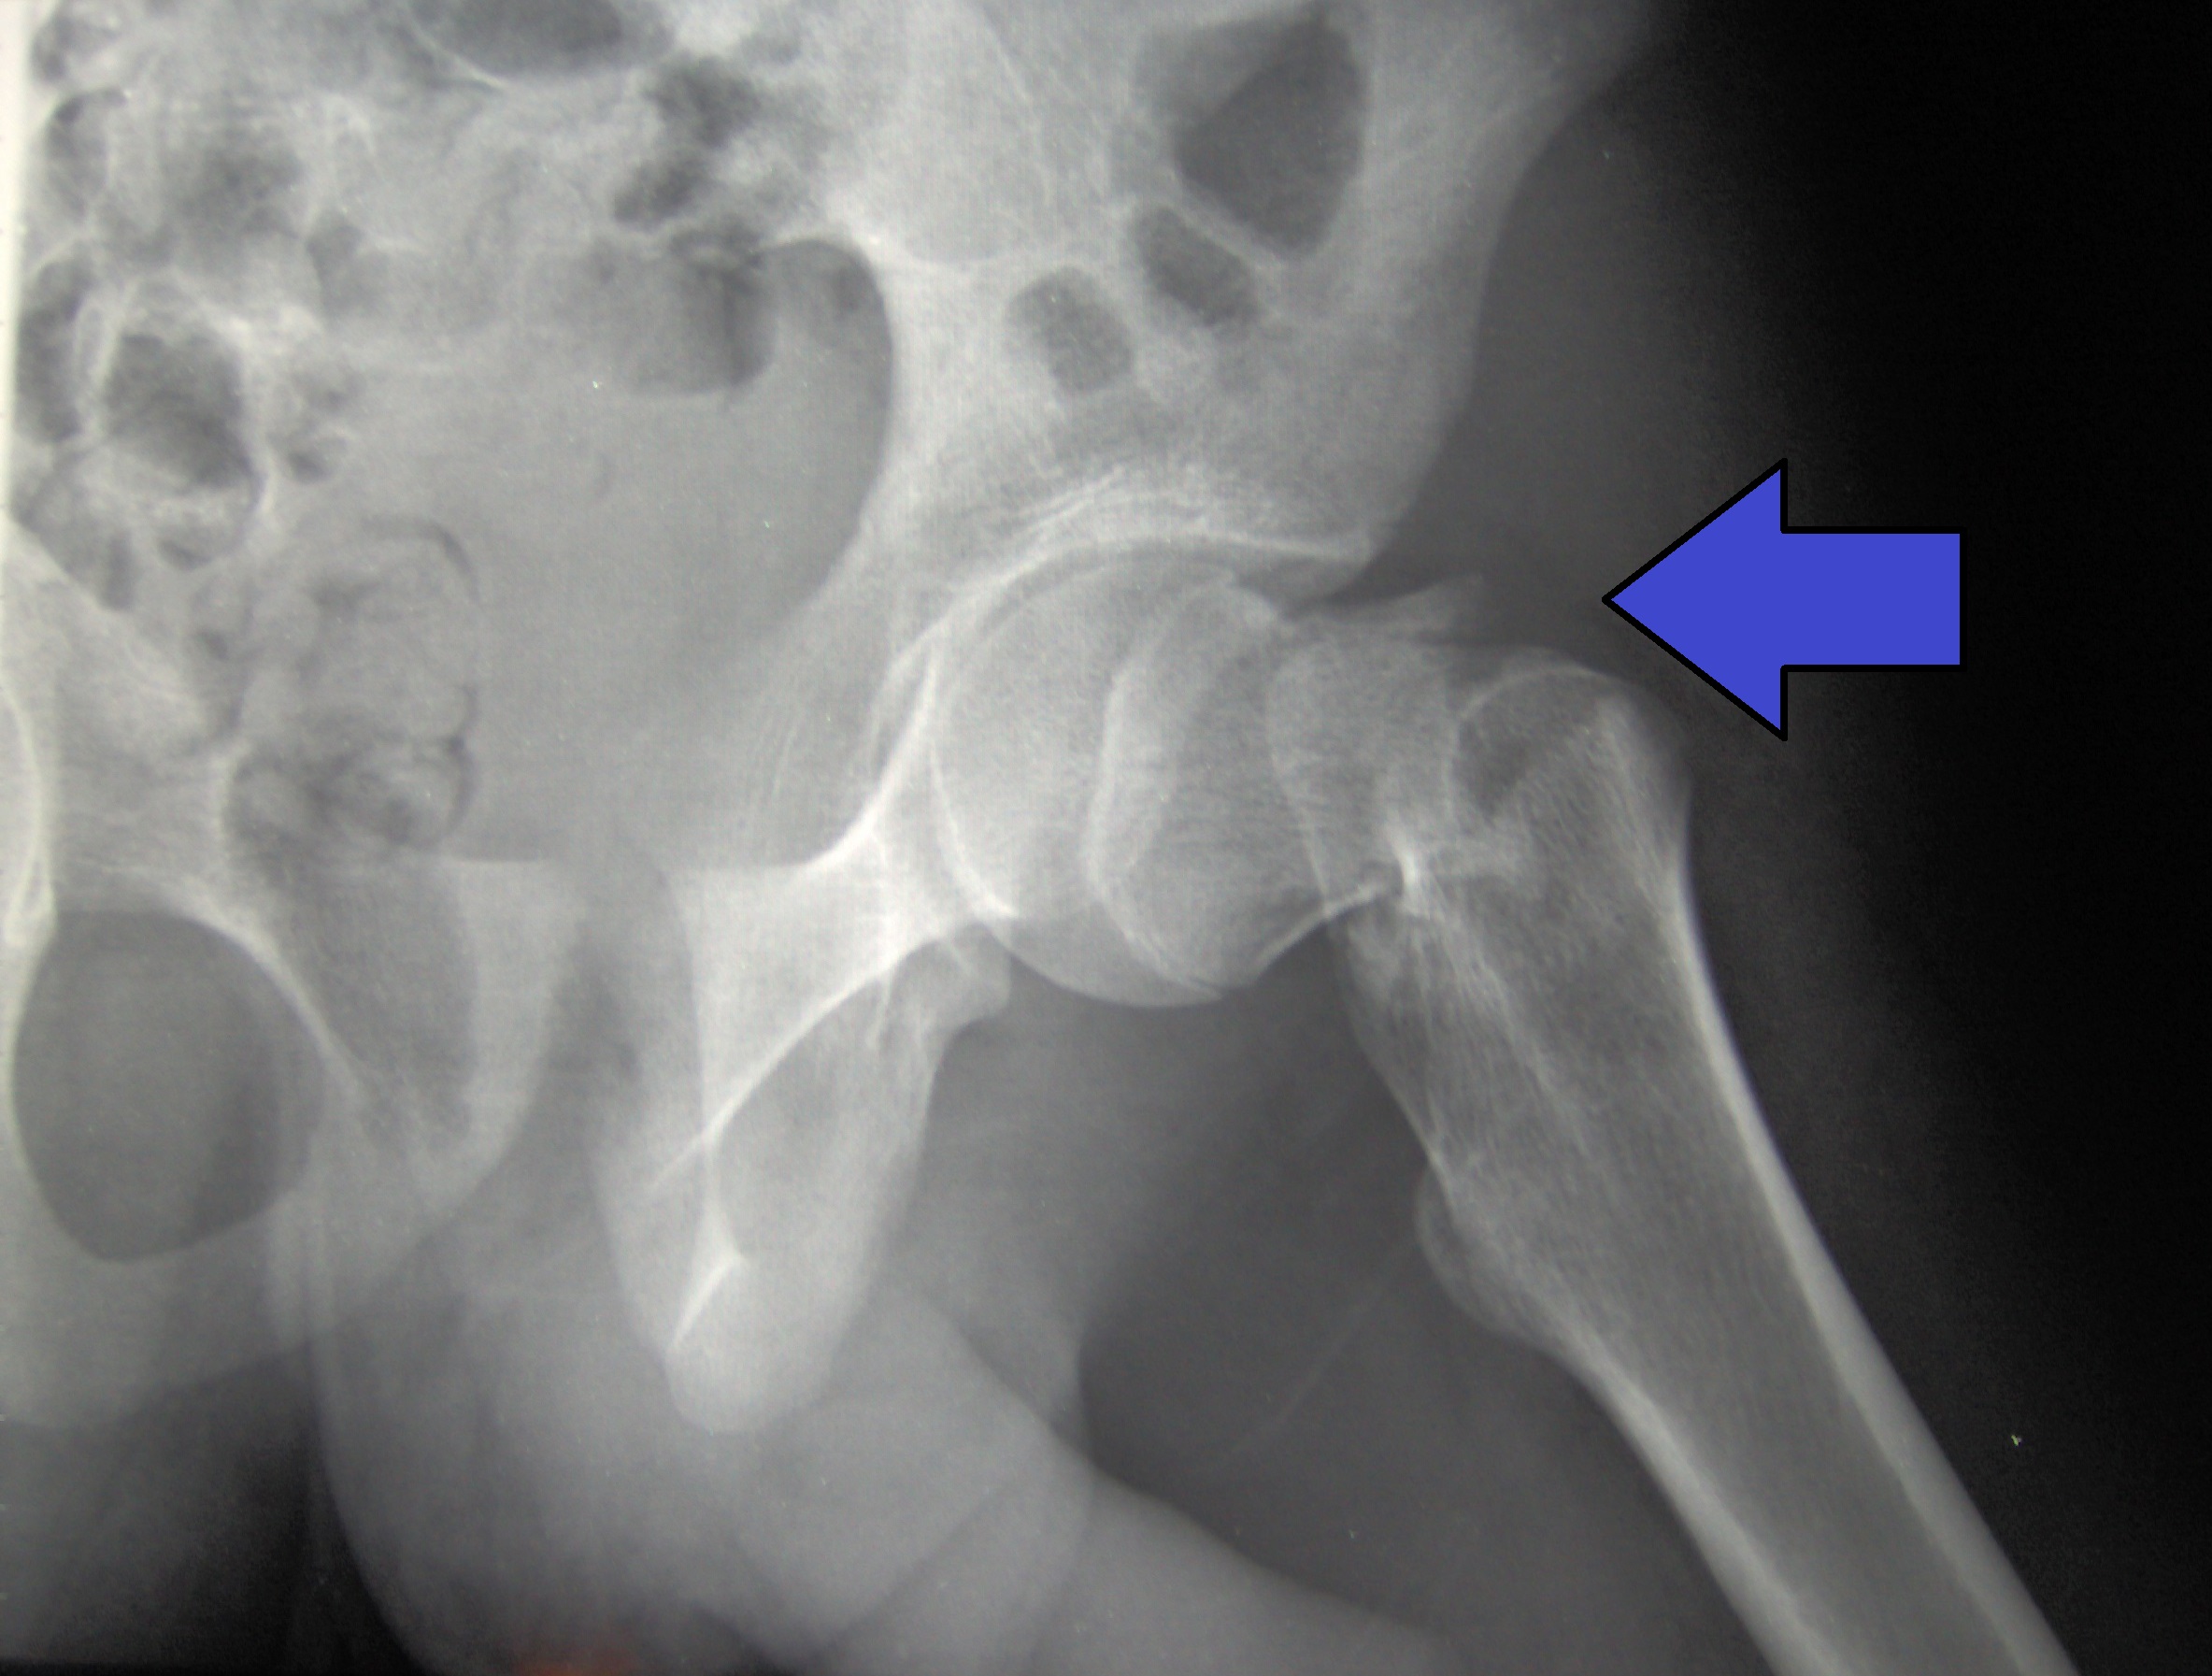

Riesgo de una nueva fractura en mujeres postmenopaúsicas según la intensidad del traumatismo inicial

15 junio 2021